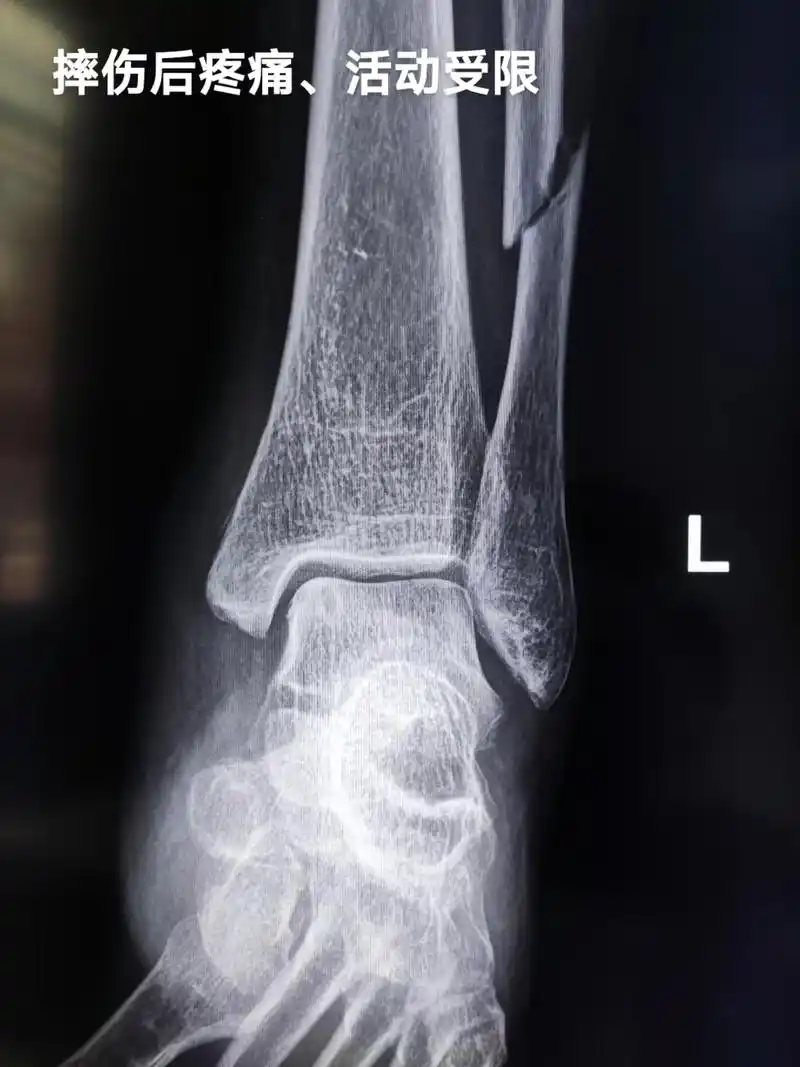

一例腓骨下极撕脱骨折

腓骨下段骨折踝关节半脱位